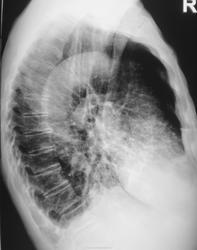

Это конечно шутка, а на самом деле здесь пневмония на фоне порока развития правого легкого. Справа внизу множественные ячейки. Ну и последствия травмы справа. Пневмония, думаю - дело временное.

Типа «сотовое лёгкое»? Нет? интересно, как оно выглядело до болезни?

Неоднозначно всё

Диф Ds поликистоз

бронхоэктазы

пневмосклероз с развитем сотового лёгкого?

Пневмония (возможно грибковая)

Я никак не могу разглядеть просвет среднедолевого бронха, проходим ли он в должной степени? Очень интересно было бы посмотреть контроль